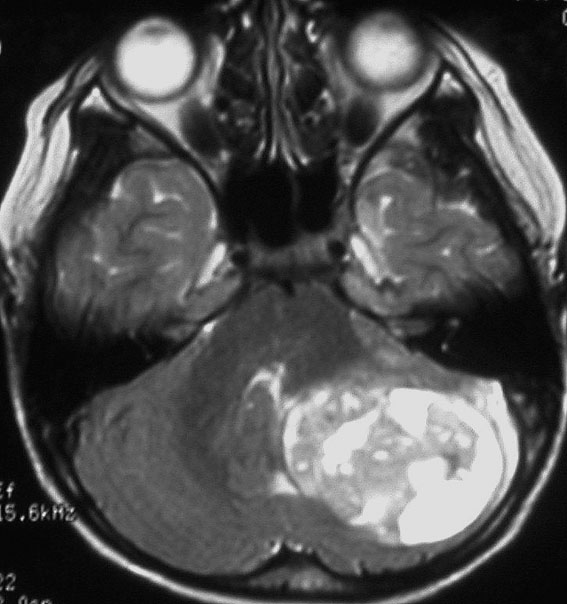

典型的な小脳虫部(小脳の真ん中)の髄芽腫です。横の方,ルシュカ孔へ伸びていないので上衣腫と区別できます。ガドリニウムという造影剤で白く写っています。